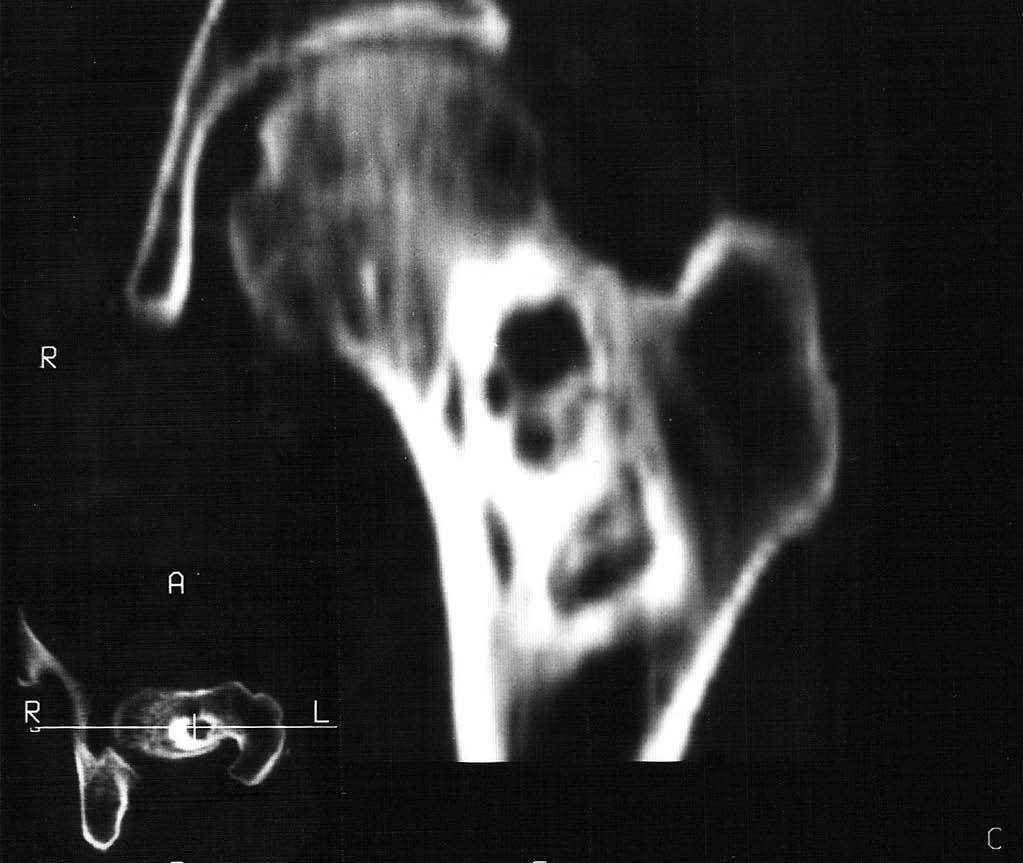

Se realizó a continuación un estudio mediante tomografía computarizada (TC) (fig. 2), obteniendo cortes axiales sin contraste y posteriores reconstrucciones multiplanares. Los hallazgos eran similares a la radiografía simple, mostrando una lesión lítica, mínimamente expansiva y con septos gruesos, sin provocar destrucción de la cortical ni masa de partes blandas, y provocando un leve festoneado endostal. En este caso no se realizó resonancia magnética (RM) y se practicó una biopsia percutánea con el resultado histológico de fibroma desmoplásico. A continuación se le realizó una biopsia quirúrgica y fue tratada mediante curetaje y relleno de la cavidad con cemento tipo Norian.

Fig. 2.--Tomografía computarizada (imagen axial y reconstrucción coronal). Se identifica un reborde grueso esclerótico y finos septos internos sin lisis de la cortical o reacción perióstica.